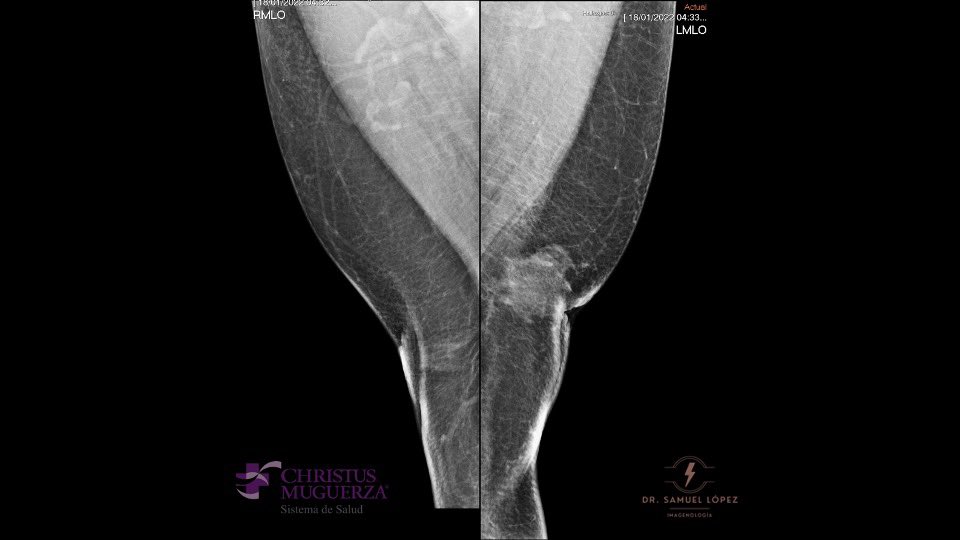

Mammography

The standard mammographic views are craniocaudal, mediolateral oblique of each breast [11] There are three characteristic patterns of gynecomastia seen at mammography which are nodular, dendritic, and diffuse glandular. [12]

The nodular pattern of gynecomastia (early, florid phase) is indicative of the presence of gynecomastia less than 1 year. Mammography will detect a nodular subareolar density. [12]

Dendritic gynecomastia (quiescent fibrotic phase) is seen in patients with gynecomastia for longer than 1 year. Histologically there will be stromal fibrosis and dilated ducts. Usually these tissue changes are irreversible. Mammograms of this phase typically show a triangular flame-shaped subareolar density with prominent linear projections permeating the surrounding tissue toward the upper-outer quadrant.[12]

Glandular gynecomastia can be seen in patients taking exogenous estrogen. Mammography will reveal enlargement of the breast and diffuse density with both dendritic and nodular features. [12]